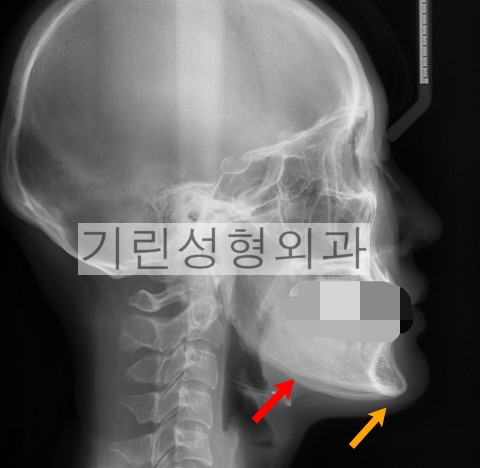

*빨간화살표: 절골된 범위. 노란화살표: V라인효과를 위해서 절골되어야 하는 범위.

위 엑스레이사진을 통해 정면효과가 없는 이유에 대해서 말씀드리겠습니다. 사례에서 귀밑각이 잘려나간 범위는 붉은화살표까지로 앞턱의 개선이 없어 당연히 정면효과 및 브이라인효과가 떨어질 수 밖에 없는 것입니다. 수술은 반드시 노란색화살표까지 절골되거나 앞턱수술이 병행되어야 만족할만한 예후를 기대할 수 있습니다.

동일인의 파노라마입니다. 역시 붉은선으로 표시된 범위가 절골된 범위로 확인됩니다.